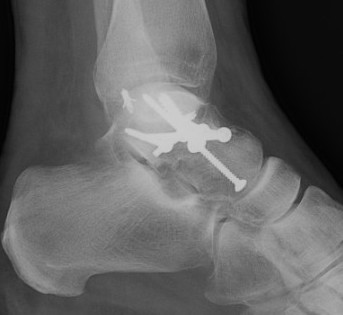

Cannulated screws

Xrays

| AP | Lateral | Canale View |

|---|---|---|

| Entry point of the screws |

Evaluate neck reduction

|

Evaluates the neck reduction |

Lateral off articular surface Medial through articular cartilage |

Depth of screws |

Beam angled 75o to foot Foot 15o pronated |

2. Antegrade (posterior to anterior) screws

- between FHL and peroneals

- entry point lateral tubercle talus

- bury to avoid posterior impingement

Antegrade screws